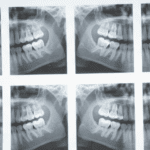

Dia Mundial da Saúde Bucal mobiliza ação na Avenida Paulista

A Dental Speed, em parceria com a ABIMO, marcou presença no evento que movimentou a capital paulista com distribuição de kits e o...